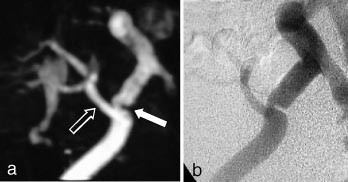

Kontrastforsterket MRA har foreløpig for dårlig romoppløsning for intrakranialt bruk. Den MRA-metoden som er best egnet for fremstilling av intrakraniale arterier, er 3D-innstrømnings-MRA (fig 3). Ved hjelp av denne metoden kan man påvise stenoser og okklusjoner av de større arteriene. Både MRA og CT-angiografi kan fremstille intrakraniale aneurismer med diameter på 5 mm eller mer med stor nøyaktighet (10, 11), for mindre aneurismer synes CT-angiografi å være noe bedre enn MRA. De ikke-invasive metodene kan bidra ved planlegging av behandling av aneurismer (kirurgisk eller radiologisk intervensjon), men metodene har ennå ikke kunnet erstatte kateterangiografi (12). Ved intrakraniale arteriovenøse malformasjoner er MR-snittbilder den metoden som best viser den anatomiske lokaliseringen av nidus (13). MRA kan gi en bedre anatomisk oversikt over hele malformasjonen, særlig om man benytter fasekontrast-MRA, som gir best fremstilling av både arterie- og venesiden. Både kirurgi og endovaskulær embolisering krever imidlertid en detaljfremstilling som bare kan gis av kateterangiografi.

Arteriosklerotisk sykdom i halsarteriene er en av de vanligste indikasjonene for MRA. Ultralydundersøkelse (med fargedoppler og spektraldoppler) er et godt ikke-invasivt alternativ, og for stenoser i carotisbifurkaturen synes denne metoden å være nokså likeverdig med MRA (14). Ultralydundersøkelsens svakhet i forhold til MRA er begrenset anatomisk dekning, verken den intrakraniale del av halsarteriene eller avgangen fra aortabuen kan fremstilles adekvat. Fremstillingen av vertebralisarteriene blir også ufullstendig. Inntil nylig har innstrømnings-MRA vært den foretrukne MRA-metoden for fremstilling av carotis- og vertebralisarteriene, men den er i ferd med å bli erstattet av kontrastforsterket MRA. Sistnevnte metode er mindre ømfintlig enn innstrømnings-MRA for ulike artefakter, som bl.a. kan føre til overestimering av stenosegrad, og den kontrastforsterkede varianten gir også en mye bedre fremstilling av arterieavgangene fra aorta (fig 5). MR med innstrømnings-MRA kan erstatte kateterangiografi ved mistanke om carotisdisseksjon (15), det er foreløpig liten erfaring med kontrastforsterket MRA ved denne indikasjonen. Kontrastforsterket MRA gir en god fremstilling av a. subclavia og er et godt alternativ ved spørsmål om stenose i skalenusporten. To kontrastinjeksjoner med redusert dose gjør det mulig å undersøke arterien med både løftet og senket arm i samme seanse. Halsvenene kan fremstilles med 2D-innstrømnings-MRA eller med kontrastforsterket MRA, men der det er spørsmål om trombosering eller venens relasjon til en tumor, vil ofte ultralydundersøkelse være tilstrekkelig. MRA gir imidlertid en bedre anatomisk oversikt og er også mer reproduserbar. 2D-innstrømnings-MRA er også